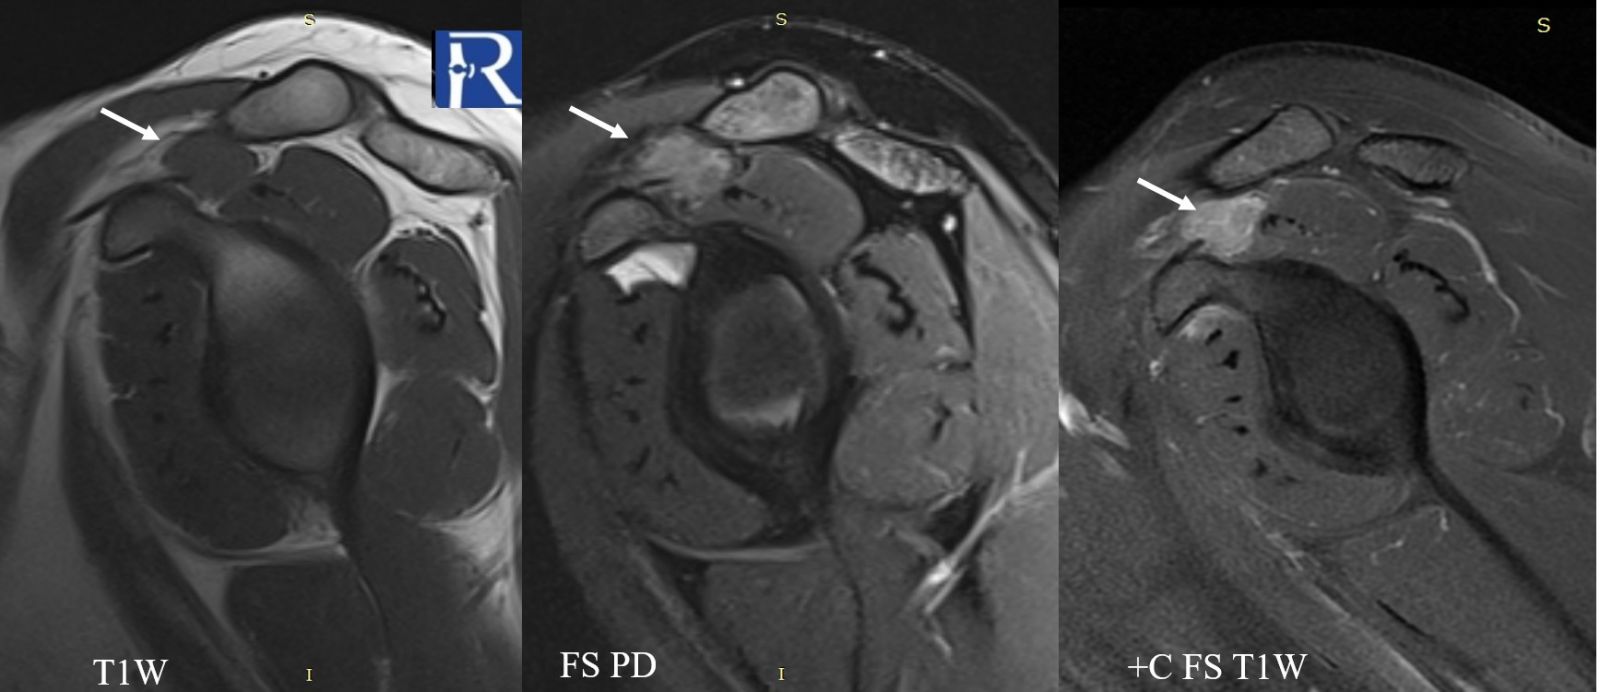

- The lesion is isointense to muscle on T1-weighted images.

- On fat-suppressed proton density sequences, the mass demonstrates intermediate to low signal intensity.

- Following contrast administration, the lesion shows marked diffuse enhancement.

- On fluid-sensitive (fat-suppressed) sequences, the lesion again exhibits intermediate-to-low signal, suggestive of hemosiderin or cellular lesion.

The combination of location adjacent to tendon/synovial structures, signal characteristics, and contrast enhancement pattern raised the suspicion for a tenosynovial giant cell tumor (TGCT).

MRI Characteristics:

- Well-circumscribed, nodular soft-tissue mass

- Intermediate to low signal on T1 and T2 sequences

- Variable hemosiderin content may cause focal low signal areas

- Enhancement after contrast is typical

- Relationship to tendon sheath/synovium is an important clue